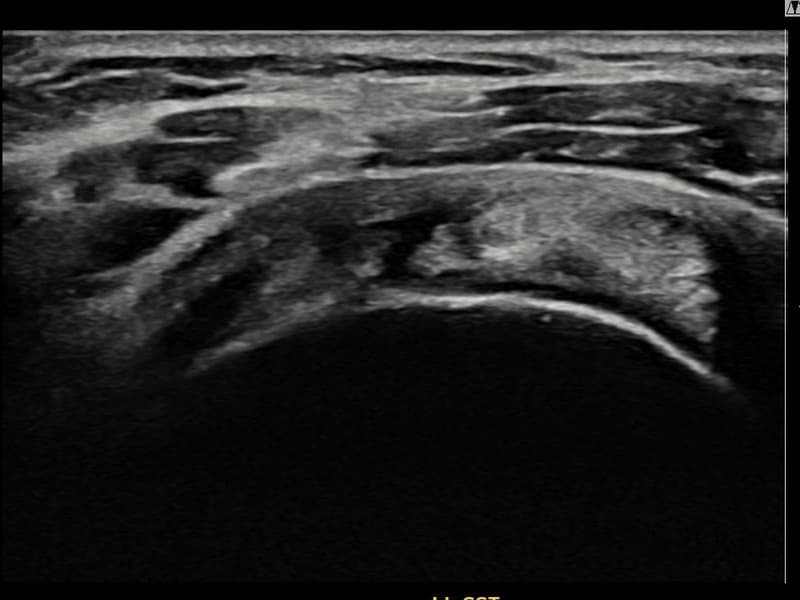

术前

术前超声确认左侧 冈上肌腱 滑囊面侧部分撕裂,左侧冈上肌腱回声不连续伴肌腱缺损(14mm × 7mm (肌腱厚度约65%缺损))。术后超声显示撕裂部位充满再生组织,肌腱连续性恢复,回声模式正常化。